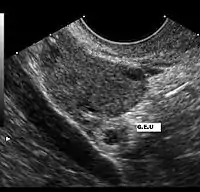

Imagerie

L'échographie par sonde abdominale permet de visualiser une masse hétérogène latéro-utérine, constitué par le sac gestationnel en dehors de la cavité utérine. L'utérus est vide mais ses parois épaissies. Un épanchement au niveau du cul-de sac de Douglas peut être mis en évidence. Cet examen a une très bonne sensibilité pour le diagnostic mais une spécificité moins importante[8].

Des β-HCG supérieurs à 4000 UI/l sans visualisation du sac ovulaire intra-utérin signent pratiquement la grossesse extra-utérine.

L'examen échographique peut être complété par l'utilisation d'une sonde endovaginale, permettant de mieux visualiser trompes, ovaires et contenu utérin et d'avoir une précision diagnostique plus importante[9].